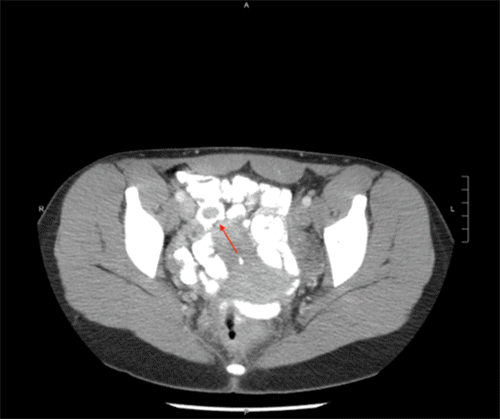

She underwent an EGD and colonoscopy, which was notable for a 30 mm polypoid appearing lesion coming from the appendiceal orifice (Figure 1) and an otherwise normal colon. Biopsies of the lesion showed fragments of colonic mucosa with hyperplastic change, fibrosis, crypt architecture distortion, and focal mild acute and chronic inflammation. A CT showed a tubular structure within the cecum measuring approximately 5 cm in length and 1 cm in width, concerning for an inverted appendix (Figure 2).

Figure 2. CT Image Demonstrating Inverted Appendix. Published with Permission

The vague abdominal pain and hematochezia exhibited in this case made an immediate diagnosis difficult. As such, she underwent a workup involving several modalities, which is common among cases of appendiceal intussusception in the literature.7,8,10‒12,16 Colonoscopy, while invasive, provided direct visualization of the mass and allowed for biopsies to be taken; ultimately, a CT was performed, which was highly suggestive of appendiceal intussusception. CT, ultrasound, and colonoscopy are the most commonly used modalities for modern assessment. However, barium studies were frequently used when such modalities were not readily available and typically showed a cecal filling defect.7,8 Given her persistent abdominal pain and inability to definitively rule out malignancy, she underwent surgical intervention, revealing the nature and etiology of her appendiceal mass. A gross examination of the specimen (Figure 4) identified this case as a type I, based on the McSwain classification.5